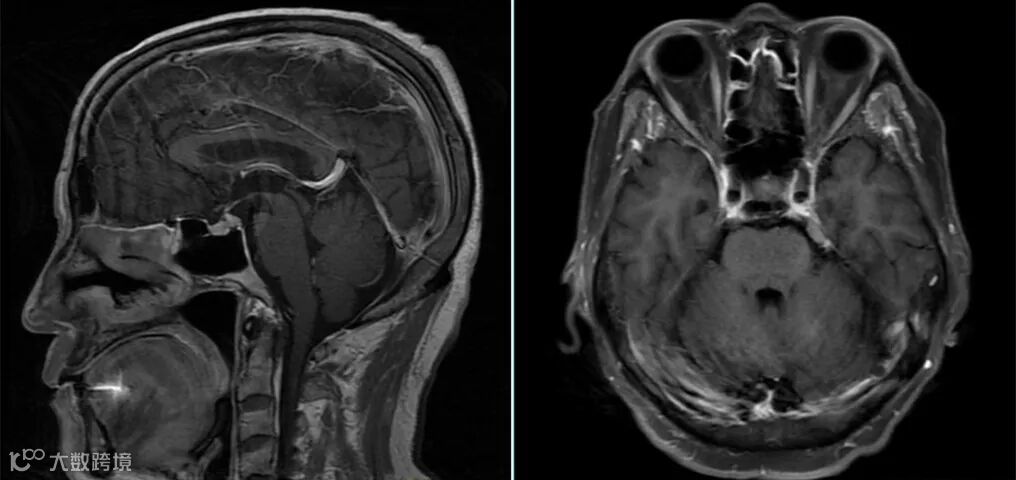

但该序列上血管同样会呈现为高信号,并不利于血管与强化病灶间的鉴别。在3D T1梯度回波序列上血管呈高信号,并不利于与强化病灶的鉴别诊断,如上图△左所示病灶可能会被误认为血管信号。 -

该序列虽然灰白质对比度不及磁化准备的3D T1梯度回波序列,但其增强后快速流动的血液呈现为低信号的“黑血”表现,更有利于血管与强化病灶间的鉴别。 -

如上一病例;图△左为3D T1磁化准备梯度回波序列,图右为3D可变翻转角的T1 自旋回波序列。